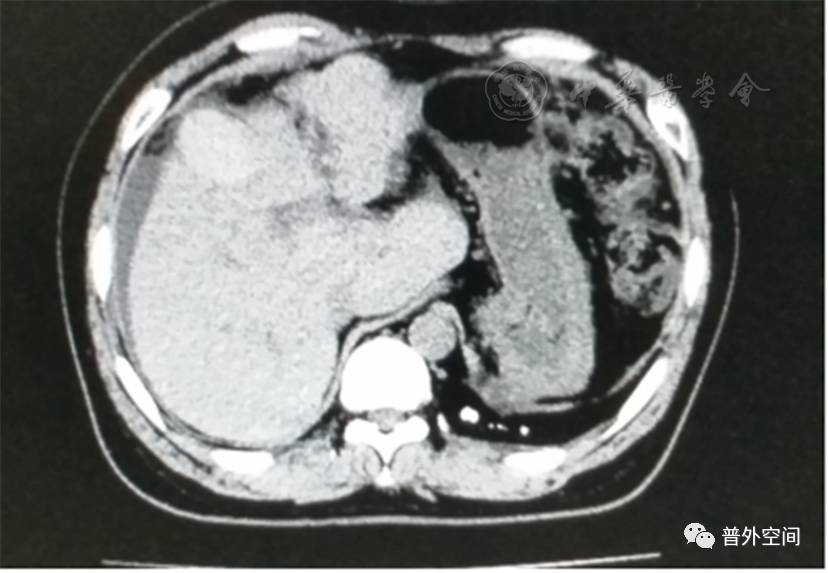

我们将这种方法应用到100多例没有艾滋病病毒感染的一般肝硬化患者身上,结果收到更好的疗效。例如1例男性患者,56岁,失代偿期肝硬化大量腹水合并脐疝(见封四,图1)。CT检查提示肝脏明显萎缩,肝脏体积1 302 ml,大量腹水,脾脏肿大(见封四,图2)。在多家医院就诊后都认为需要做肝移植。我们对患者进行脾切除加脐疝修补,自体骨髓经门静脉输注治疗。手术后3个月,肝功能Child-Pugh分级从C级转成*级A**,手术后1年,肝功能正常,腹部伤口愈合良好(见封四,图3)。CT检查提示肝脏明显增大,体积1 796 ml,腹水基本消失(见封四,图4)。针对肝功能C级的患者手术风险比较高,围手术期输注白蛋白、凝血酶原复合物、纤维蛋白原,改善肝脏功能,手术中经胃网膜右静脉插管埋置骨髓输注装置,输注自体骨髓。随着自体骨髓干细胞在肝内发生复杂的变化,肝硬化组织中的胶原纤维被降解和吸收,肝脏组织的增生和体积增大,肝功能好转,门静脉压力会逐渐降低。但是在手术后1年内,仍然有可能随时发生上消化道出血,需要经胃镜检查,套扎食管黏膜下明显曲张的静脉血管。这样我们做脾脏切除解除脾功能亢进,不做贲门周围血管离断,减少了手术损伤。食管黏膜下静脉曲张用胃镜下套扎治疗。待肝硬化逐渐逆转,食管黏膜下静脉曲张程度将会逐渐减轻。

图4 1年后对比手术前同一部位CT断层照片